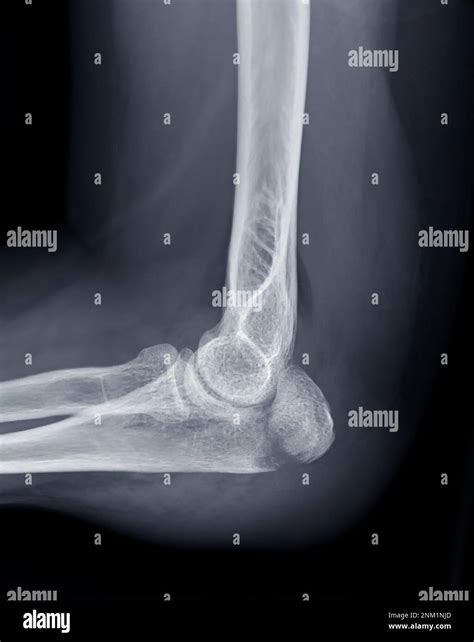

Not all cubitus fractures are the same. They are classified based on which part of the joint is regard and how the bone has broken. Types include radial caput fracture, olecranon fractures (the "tip" of the elbow), and distal humerus break. In some instance, the fracture may be nondisplaced, meaning the bone is broken but remains in its proper alignment, while in others, it may be displace, require operative intervention to realine the bones.

Tomography is the fundament of diagnose a crack in the cubitus. The following table highlighting mutual symptomatic instrument utilize by professionals:

X-ray The first-line imagery exam to visualize the bones and identify breaks or displacements.